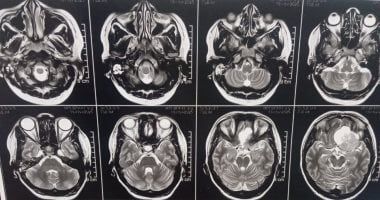

وأوضح الدكتور مجدي القاضي، عميد كلية الطب البشري ورئيس مجلس إدارة المستشفيات الجامعية، أن المريضة كانت تعاني من صداع شديد وارتفاع ضغط المخ وتدهور في حدة الإبصار، وبإجراء الفحوصات الطبية وأشعة الرنين المغناطيسي، تبين وجود ورم كبير بقاع الجمجمة يضغط على أعصاب البصر والأوعية الدموية المغذية للمخ، ما استدعى التدخل الجراحي العاجل باستخدام أحدث التقنيات الدقيقة.